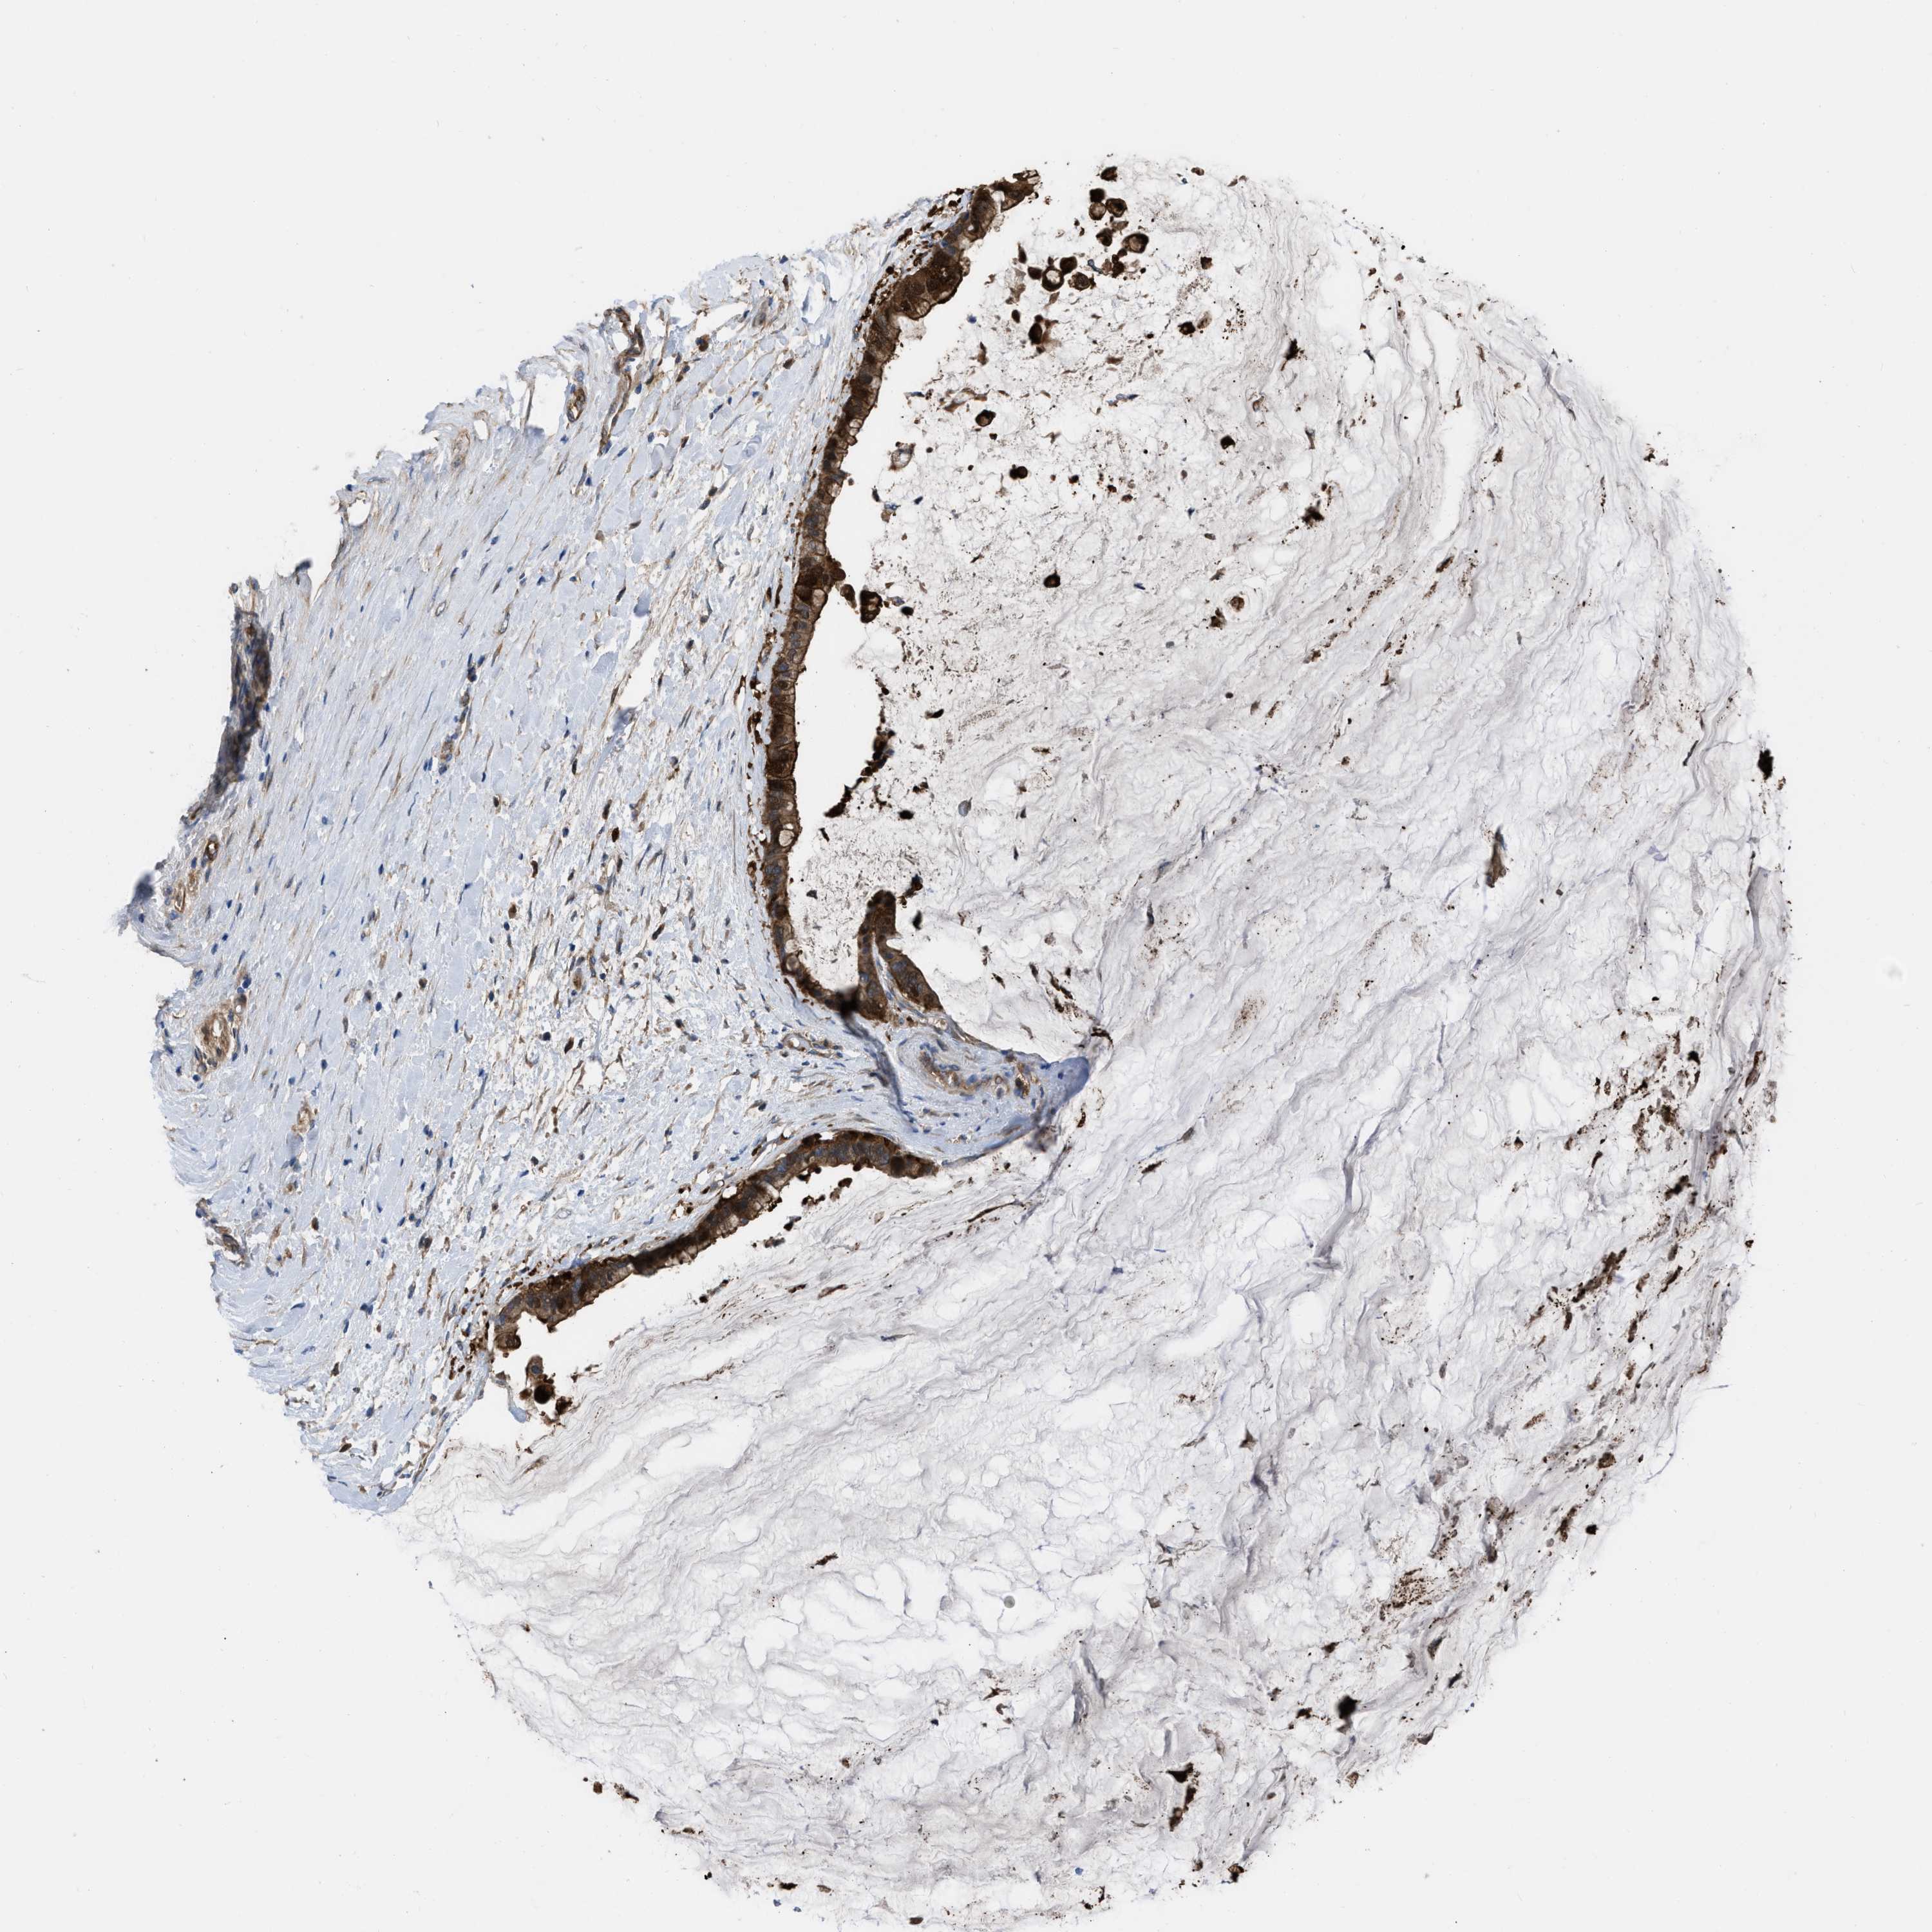

PANCREATIC CANCER - Protein expressioni

A mouse-over function shows sample information and annotation data. Click on an image to view it in a full screen mode. Samples can be filtered based on level of antibody staining by selecting one or several of the following categories: high, medium, low and not detected. The assay and annotation is described here.

Note that samples used for immunohistochemistry by the Human Protein Atlas do not correspond to samples in the TCGA dataset.

Antibody stainingi

Antibody staining in the annotated cell types in the current human tissue is reported as not detected, low, medium, or high, based on conventional immunohistochemistry profiling in selected tissues. This score is based on the combination of the staining intensity and fraction of stained cells.

Each image is clickable and will lead to virtual microscopy that enables deeper exploration of all samples and also displays staining intensity scores, fraction scores and subcellular localization as well as patient and tissue information for each sample.

Antibody HPA003747

Antibody HPA019769

Staining

High

Medium

Low

Not detected

Intensity

Strong

Moderate

Weak

Negative

Quantity

>75%

75%-25%

<25%

None

Location

Nuclear

Cytoplasmic/membranous

Cytoplasmic/membranous,nuclear

Adenocarcinoma, NOS

Adenocarcinoma, metastatic, NOS